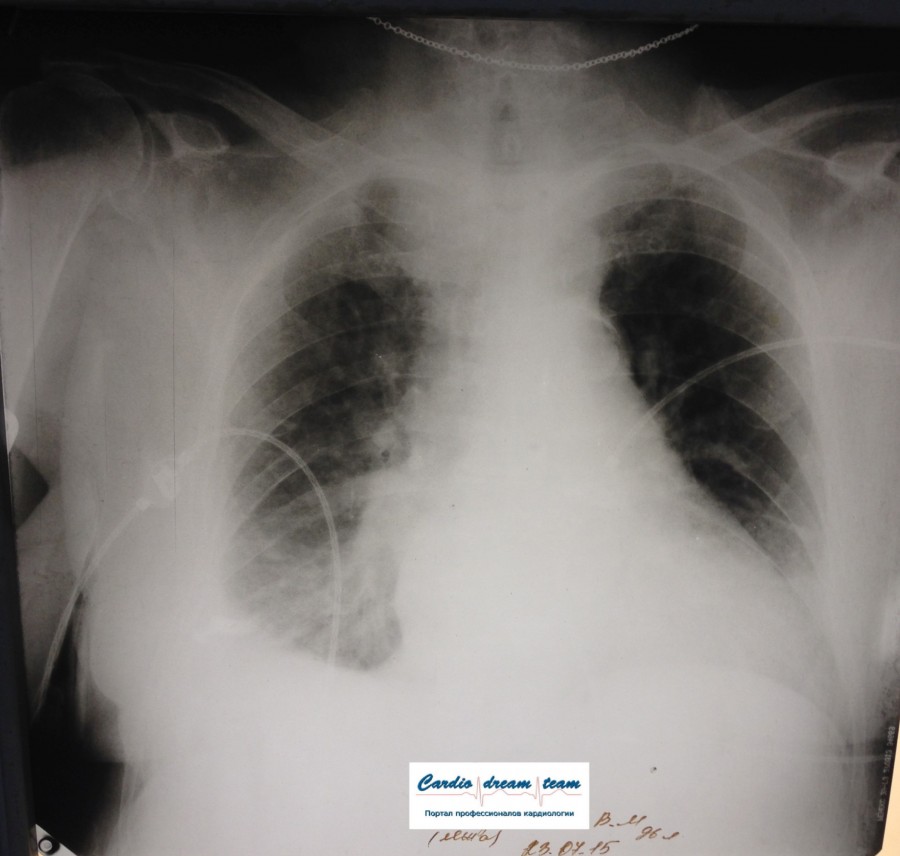

Не обсуждалась Дата 23-ИЮЛ-15 ОПИСАНИЕ: Проведена рентгенография органов грудной клетки в прямой проекции, положение лежа, условия ПИТ Легочные поля: неравномерно прозрачны за счет сосудистого обогащения, в базальных отделах с обеих сторон, отмечается сгущение легочного рисунка, за счет гиповентиляции, в плевральных полостях жидкость Легочный рисунок: Изменен по смешанному типу: обогащен за счет сосудистого компонента, деформирован за счет склероза. Корни: бесструктурны, расширены за счет сосудистого компонента, обогащены Синусы: определяется наличие жидкости по линии 5 ребра Сердце: широко лежит на диафрагме отмечается расширение границ сердечной тени влево, вправо экг-электроды. ЗАКЛЮЧЕНИЕ: Рентген-признаки 2-х стороннего гидроторакса с гиповентиляцией базальных сегментов.. Признаки застоя по МКК 2 степени (умеренно выраженный). Пневмосклероз. Р-признаки гипертрофии левого желудочка сердца. Склероз аорты.

IMG_4339--.jpg [ 717.06 KiB | Просмотров: 29545 ]